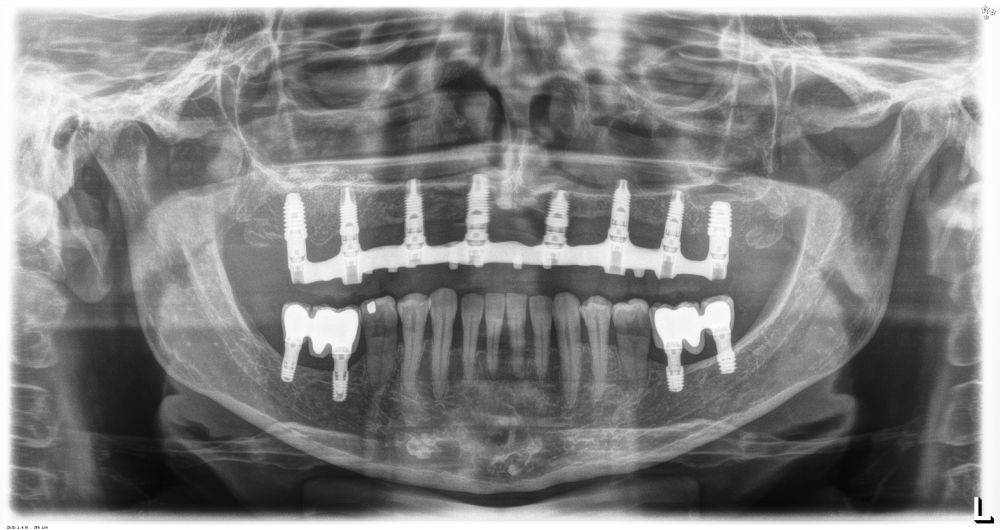

Fueron reclutados pacientes de forma retrospectiva con atrofia ósea horizontal severa (con anchura residual de cresta menor o igual a 3 mm), donde se colocasen injertos en bloque para regeneración ósea y posteriormente se insertarán implantes, con un tiempo de seguimiento tras la carga mayor o igual a 10 años. Antes de la colocación de los implantes, todos los pacientes fueron sometidos a una evaluación integral que incluyó modelos diagnósticos, un examen clínico intraoral detallado y un estudio tomográfico mediante Cone beam (TAC dental). Las imágenes obtenidas fueron analizadas con un software especializado (BTI-Scan III) para garantizar una planificación tridimensional precisa. Posteriormente, se llevó a cabo un encerado diagnóstico que sirvió como base para la creación de una guía quirúrgica, optimizando la ejecución de la rehabilitación planificada. La posición final de los dientes obtenida del encerado será la que guíe el proceso de regeneración para lograr el volumen óseo necesario para colocar los implantes en la posición necesaria. Antes de la inserción de los implantes se utilizó una pre-medicación antibiótica consistente en amoxicilina 2gr vía oral una hora antes de la intervención y paracetamol 1 gramo vía oral (como analgésico). Posteriormente los pacientes prosiguieron con un tratamiento de amoxicilina 500-750 mg vía oral cada 8 horas (según peso) durante 5 días. Todos los injertos se obtuvieron de rama mandibular y fueron divididos en cortical y esponjosa, según la técnica de Khoury18. Se conservaron en PRGF-Endoret hasta el momento de su uso y el hueso particulado obtenido de la parte medular del injerto se colocó embebido en PRGF-Endoret fracción 2 sin activar. Una vez posicionados los injertos fueron fijados mediante material de ostesíntesis (KTOÒ– Biotechnology institute) y toda la zona intervenida se cubre con membranas de fibrina autóloga (PRGF-Endoret fracción 1 activada y retraída) antes de la sutura con monofilamento de 5/0 para lograr cierre primario. Los injertos maduran 4-5 meses y posteriormente se realiza un nuevo Cone beam para conocer la anchura lograda y planificar la inserción de los implantes. La inserción de los implantes fue realizada por un mismo cirujano, mediante la técnica de fresado biológico, a bajas revoluciones, sin irrigación26-28. Una vez transcurridos cuatro meses desde la inserción de los implantes, se lleva a cabo la carga de los mismos mediante una prótesis provisional de carga progresiva elaborada en resina, con estructura metálica de barras preformadas y atornillada a transepiteliales. Estas prótesis provisionales se mantienen de 3 a 6 meses, en función de la adaptación y requerimientos de cada paciente. Una vez transcurrido este tiempo se realizan las prótesis definitivas. Tras la colocación de las prótesis definitivas los pacientes entran en un programa de seguimiento al que acuden cada 6 meses. En estas visitas se realizan radiografías panorámicas de control y periapiacales en la zona de inserción de los implantes. Las radiografías periapicales se llevan a cabo con posicionador, para generar imágenes reproducibles y los pacientes son colocados para la radiografía panorámica con posicionador fijo en glabela y mentón, mordedor para zona interincisal con eje de línea media, plano bipupilar y frackfort (marca láser) y con los pies sobre marcas trazadas en el suelo, con el propósito de que sean altamente reproducibles los resultados. Sobre estas radiografías se llevan a cabo las mediciones necesarias para comprobar la estabilidad y pérdida ósea crestal de los implantes. Una vez obtenida la radiografía en formato digital es calibrada mediante un software específico (ImageJ) a través de una longitud conocida como es el implante dental. Una vez introducimos la medida de calibración, el programa informático realiza un cálculo basado en esta medida para eliminar la magnificación, pudiendo realizar mediciones lineales exentas de este error. En la visita final de seguimiento (10 años) se lleva a cabo un nuevo cone-beam para estimar la anchura ósea final tras el período de carga de los implantes y valorar la potencial reabsorción del volumen óseo logrado con la técnica regenerativa del injerto en bloque. El paciente fue la unidad de medida para el análisis de la edad, sexo y la historia médica. La variable principal estudiada ha sido el mantenimiento del volumen óseo logrado con la técnica regenerativa tras 10 años de carga. Como variables secundarias se han estudiado la supervivencia de los implantes y la pérdida ósea mesial y distal. La supervivencia de los implantes se calculó mediante el método de Kaplan-Meier. Los datos fueron analizados con SPSS v15.0 para windows (SPSS Inc., Chicago, IL, USA). Fue realizado un test de shapiro-Wilk sobre los datos obtenidos para constatar la distribución normal de la muestra.

Una vez regenerado el lecho óseo con los injertos en bloque, se obtiene una media de anchura de 6,77 mm (+/- 0,91), lo que supone un incremento medio de 5,35 mm para cada caso. En la figura 2 se muestra la anchura inicial y final para cada zona donde posteriormente se insertarán los implantes.

La media de la pérdida ósea mesial de los implantes estudiados en el final del período de seguimiento a los 10 años fue de 0,94mm (+/- 0,28) mientras que la media de la pérdida ósea distal fue de 0,77 mm (+/- 0,17). Durante el tiempo de seguimiento no se registró ningún fracaso en los implantes estudiados. La media de la anchura ósea a los 10 años fue de 6,26 mm (+/- 1,08). En la figura 4 se observa la diferencia entre la anchura inicial, la lograda tras la consolidación del injerto y tras los 10 años de seguimiento. En las figuras 5-19 se muestra uno de los casos incluidos en el estudio.